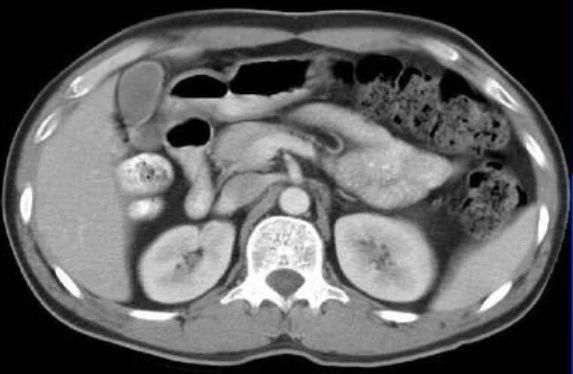

上图是一张腹部CT的图像,如果我们也像上右图那样调整对比度,也将看到一片白。显然,我们知道内脏的颜色应该是什么样的。所以“白肺”,也不是真的变白了。